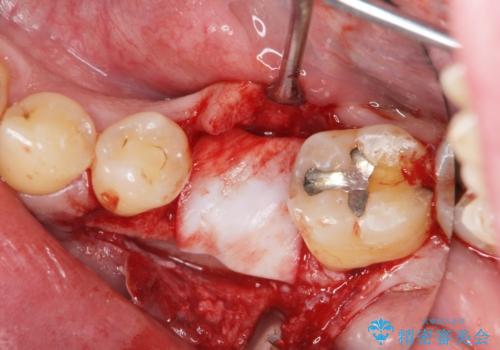

- 奥歯を失ったのち放置してしまった部位にインプラント治療を希望されて来院されました。

少量の骨造成を併用したインプラント治療を計画します。